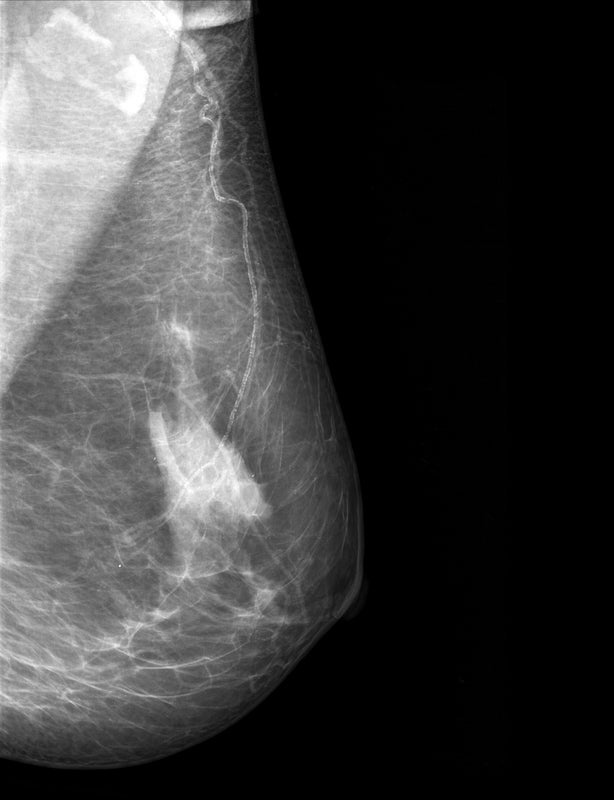

Brustkrebs wird als HER2-positiv bezeichnet, wenn die Tumorzellen sehr viele Rezeptoren des Typs HER2 haben, an denen Wachstumsfaktoren andocken, die die Zellteilung anregen. Mammakarzinome mit einer niedrigen HER2-Expression wurden bisher als HER2-negativ klassifiziert und deshalb in Studien zur zielgerichteten Anti-HER2-Therapie nicht eingeschlossen. In die Studie DESTINY-Breast04 wurden jetzt aber auch Patientinnen und Patienten mit HER2-low-Tumoren eingeschlossen – und Trastuzumab-Deruxtecan zeigte auch für diese Betroffenen eine Wirkung, sodass die Zulassung entsprechend erweitert wurde.